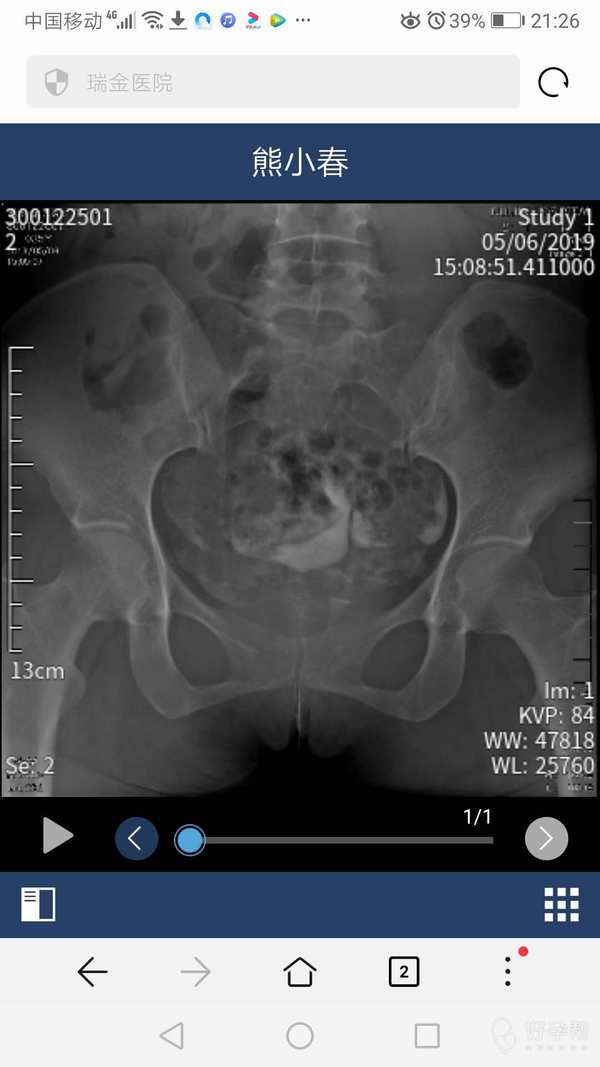

通而不畅,帮我看下怎么办,双子宫